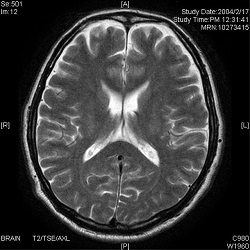

脊髄損傷を客観的に示すのに最も有効なのは、MRI(磁気共鳴画像)です。

MRIであれば、脊髄の負傷により骨の内部に生じた出血や浮腫などを撮影することができます。